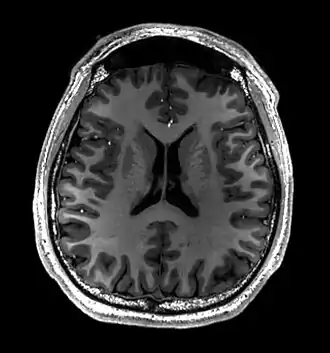

- T1-weighted (T1W) images: Cerebrospinal fluid is dark. T1-weighted images are useful for visualizing normal anatomy.

Brain regions on T1 MRI -

T1 (note CSF is dark) with contrast (arrow pointing to meningioma of the falx) -

Normal axial T2-weighted MR image of the brain -